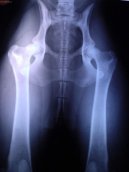

Psí plemena:  > Ortopedie - DKK (Veterinární zákroky) Ortopedie - DKK (Veterinární zákroky) - Kloubní potíže u psů se týkají z velké části vrozených vad a růstových poruch u mladých jedinců.